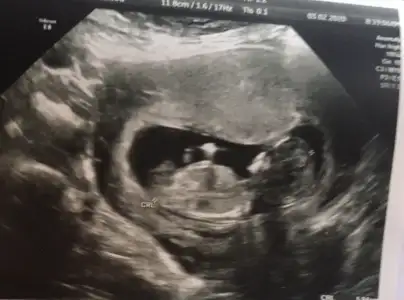

1 usg daha varsa paylaşınTeşekkürler tahminler için12+4 günlük bugün ikili testte doktor yanilabilirim ama kız dedi emin olmayınca ben de tahminleri merak etmiştim. Bakalım ilerleyen haftalarda ne olacak

Aaaa hayırlısı olsun Hepimiz erkek demişiz netleşince yaz bize deTeşekkürler tahminler için❤ 12+4 günlük bugün ikili testte doktor yanilabilirim ama kız dedi emin olmayınca ben de tahminleri merak etmiştim. Bakalım ilerleyen haftalarda ne olacak☺

Erkek gibi nubu tam dik değil ama paralelde değil oyum erkek kullanıyorum12+4 dktor %80 ihtimalle cinsiyet tahmn rtti ama emin olamadık. Sizin tahmininizi merak ediyoruz